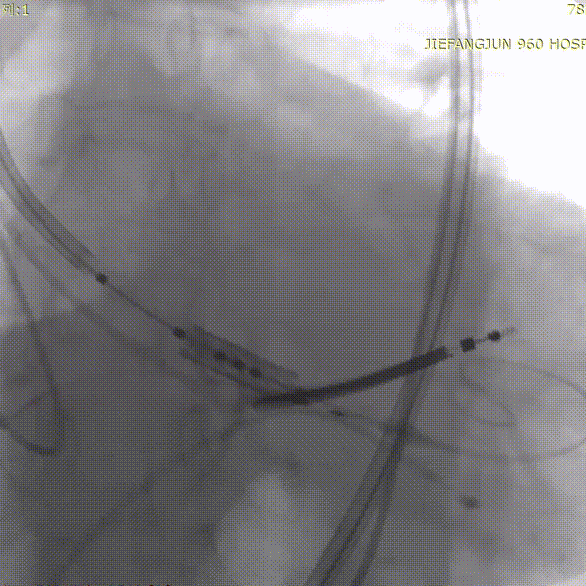

导丝跨瓣

球囊预扩

随后,沿加硬导丝送入体外预装好的Prizvalve® THV 23瓣膜,顺利过弓跨瓣,精准定位后,以180次/分快速起搏,待收缩压降到50mmHg时,2-8定位、减容策略进行释放瓣膜。

瓣膜定位造影